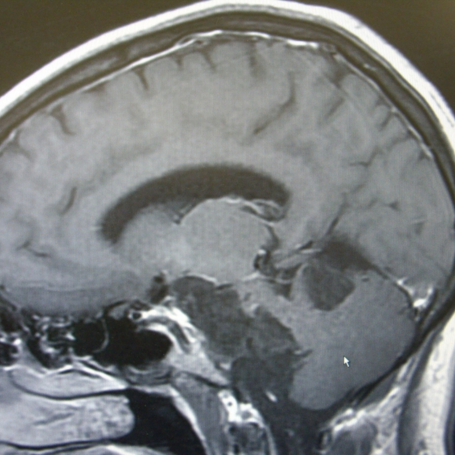

Cirugía de Quistes Cerebrales

Tipos: Incluye quistes aracnoideos, dermoides, epidermoides, coloides y pineales. Estos pueden ser congénitos o adquiridos y variar en tamaño y localización, afectando la función neurológica según su crecimiento o presión.

Diagnóstico: Se realiza mediante resonancia magnética (RM), tomografía computarizada (TAC) y evaluación neurológica. Estos estudios permiten determinar tamaño, ubicación y efecto sobre estructuras cerebrales.